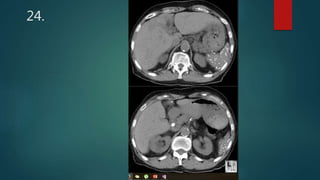

This document appears to be a medical report discussing several patients. It mentions a 35-year-old who was in a severe motor vehicle accident and an 81-year-old with a history of a non-vegetarian diet who had a perforated bowel from a chicken bone. The document provides few other details across its 25 numbered entries and was authored by Dr. Anish Choudhary for junior year 3 on May 30, 2016.